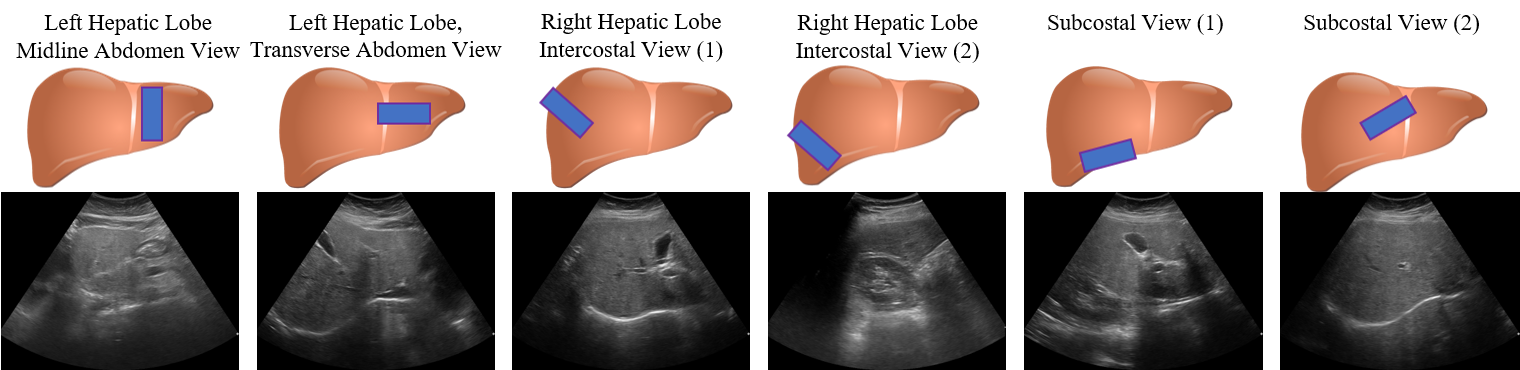

While \acHVF can effectively integrate arbitrary numbers of \acUS images within a study, it uses the same \acFCN feature extractor across all images, treating them all identically. Yet, there are certain \acUS features, such as vascular markers, that are specific to particular views. As a result, some manner of view-specific analysis could help push performance further. In fact, based on guidance from our clinical partner, \acUS views of the liver can be roughly divided into categories, which focus on different regions of the liver. These are shown in Fig 3.

A naive solution would be to use a dedicated deep \acNN for each view category. However, this would drastically reduce the training set for each dedicated \acNN and would sextuple the number of parameters, computation, and memory consumption. Intuitively, there should be a great deal of analysis that is common across \acUS views. The challenge is to retain this shared analysis, while also providing some tailored processing for each category.

Dataset. We test our system on a dataset of \acUS patient studies collected from the Chang Gung Memorial Hospital in Taiwan, acquired from Siemens, Philips, and Toshiba devices. The dataset comprises patients, among which () patients have moderate to severe fibrosis (27 with severe liver steatosis). All patients were diagnosed with hepatitis B. Patients were scanned up to times, using a different scanner type each time. Each patient study is composed of up to \acUS images, corresponding to the views in Fig. 3. The total number of images is . We use -fold cross validation, splitting each fold at the patient level into , , and , for training, testing, and validation, respectively. We also manually labeled liver contours from randomly chosen \acUS images.